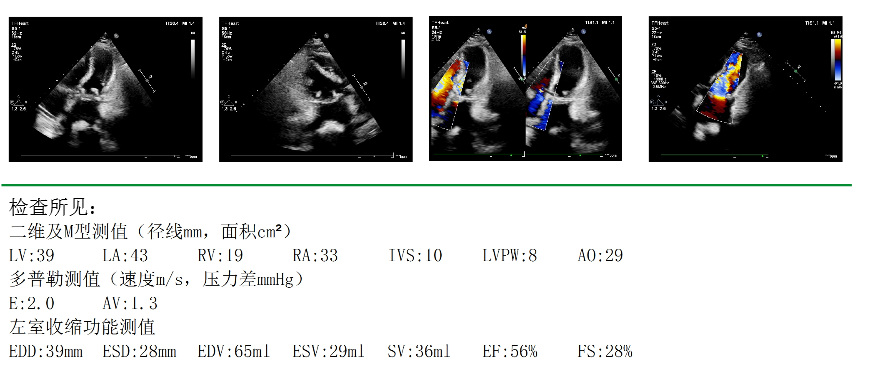

△术后心脏彩超

术后患者心律转为窦性心律,立即转入重症医学科病房,并于10月25日转回心脏大血管外科病房。在多学科团队协作下,患者身体状况恢复良好,目前已康复出院。